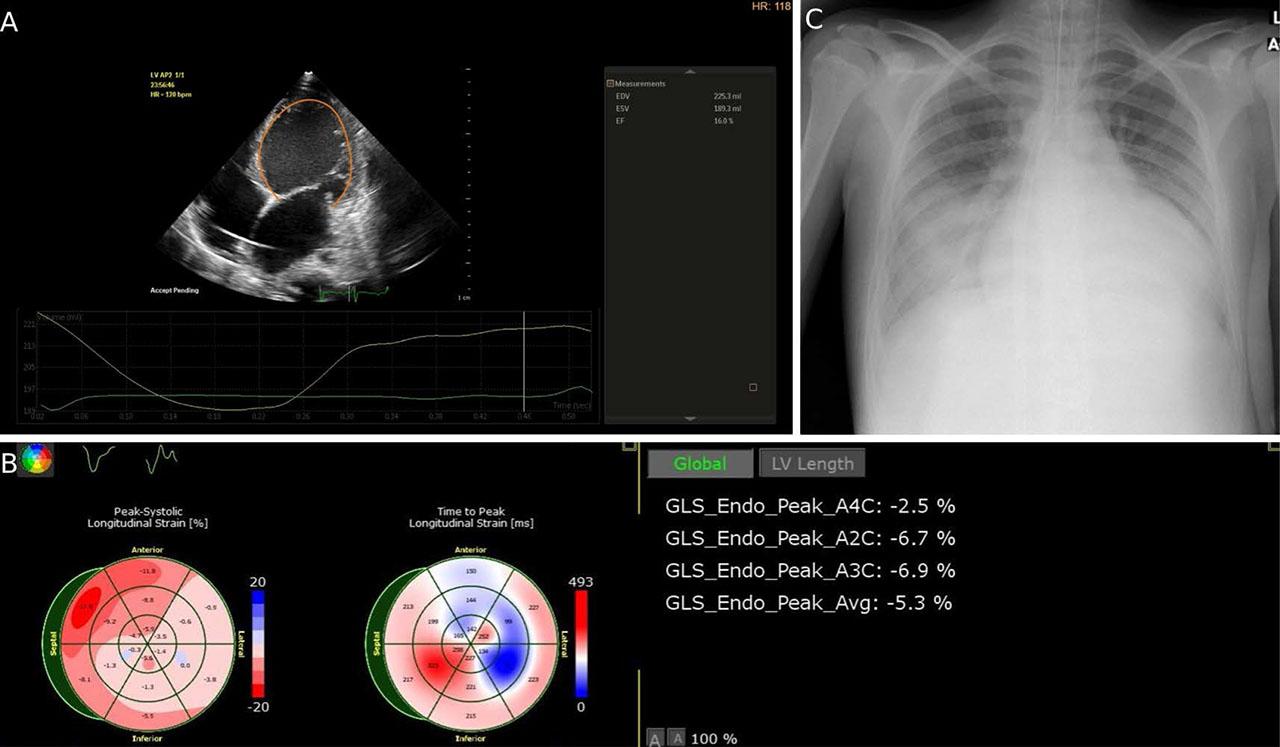

When the patient arrived to the intensive care unit he was in cardiogenic shock (orthopnea, marked hepatomegaly, hypotension, and renal failure). Transthoracic echocardiography showed a very low LVEF of 16%, decreased LV global longitudinal strain of −5.3%, right ventricular dysfunction, and aortic insufficiency (Figure 1A,B). The inotropic support was escalated, and adrenaline and milrinone were added to dobutamine. Vasopressor support with noradrenaline was also needed. However, the patient remained in a critical state, requiring mechanical circulatory support. A left ventricular assist device (LVAD) was not a suitable option because of the right heart dysfunction (poor contractility of the right ventricle, large tricuspid regurgitation); therefore, the patient received an extracorporeal membrane oxygenator (ECMO) by peripheric canulation (femoral artery and vein). However, severe congestion of the left heart was observed with pulmonary edema (Figure 1C).

Severe left ventricular dysfunction. A. Severely dilated LV with impaired systolic function (auto 2D quantification). B. Decreased LV global longitudinal strain (GLS) C. Chest radiograph revealing pulmonary edema.